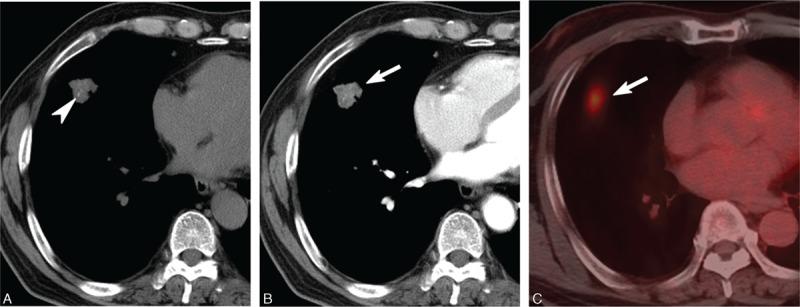

To describe the features and clinical implications of computed tomography (CT), positron emission tomography (PET), and percutaneous needle aspiration biopsy (PCNB) in pulmonary nontuberculous mycobacterial (NTM) disease manifesting as a solitary nodule, mass, or mass-like consolidation mimicking malignancy.Among a cohort of 388 patients with NTM pulmonary disease, 14 patients with clinically and radiologically suspected lung cancer were included in our study. Two chest radiologists evaluated CT features, including lesion type (nodule, mass, or mass-like consolidation), morphologic features (margin, degree of enhancement, calcification), and presence of accompanying findings suggestive of NTM pulmonary disease (bronchiectasis with clustered centrilobular nodules or upper-lobe cavitary lesions) by consensus. Diagnostic procedures for microbiologic diagnosis of NTM disease and clinical outcome were reviewed.Incidence of NTM pulmonary disease presenting as solitary nodule/mass (n = 8) or mass-like consolidation (n = 6) was 3.6% (14 of 388). Most lesions were detected incidentally during routine health check-up or evaluation of other disease (11 of 14, 79%). Lesions typically showed poor contrast-enhancement (9 of 12) and internal calcification (6 of 14). No lesions had CT features suggestive of NTM pulmonary disease. All 4 lesions for which PET/CT imaging was performed showed strong fluorodeoxyglucose uptake simulating malignant lesions (mean, 4.9; range, 3.6-7.8). PCNB revealed mycobacterial histology in 6 of 11 specimens and positive culture results were obtained for 7 of 7 specimens.NTM pulmonary disease may present as a solitary nodule, mass, or mass-like consolidation mimicking malignancy. CT features and PCNB are important to diagnose NTM disease mimicking lung cancer to avoid unnecessary surgery.

描述计算机断层扫描(CT)、正电子发射断层扫描(PET)和经皮针吸活检(PCNB)在表现为孤立性结节、肿块或类似肿块的实变影且疑似恶性肿瘤的肺非结核分枝杆菌(NTM)病中的特征及临床意义。在388例NTM肺病患者队列中,14例临床及影像学疑似肺癌的患者纳入本研究。两名胸部放射科医生通过共识评估CT特征,包括病变类型(结节、肿块或类似肿块的实变影)、形态学特征(边缘、强化程度、钙化)以及提示NTM肺病的伴随表现(伴有簇状小叶中心结节的支气管扩张或上叶空洞性病变)。回顾NTM病的微生物学诊断程序及临床结局。表现为孤立性结节/肿块(n = 8)或类似肿块的实变影(n = 6)的NTM肺病发生率为3.6%(388例中的14例)。大多数病变在常规健康检查或其他疾病评估期间偶然发现(14例中的11例,79%)。病变通常表现为强化不佳(12例中的9例)及内部钙化(14例中的6例)。无病变具有提示NTM肺病的CT特征。进行PET/CT成像的4例病变均显示强烈的氟脱氧葡萄糖摄取,类似恶性病变(平均值为4.9;范围为3.6 - 7.8)。11例标本中有6例PCNB显示分枝杆菌组织学,7例标本中有7例培养结果为阳性。NTM肺病可能表现为孤立性结节、肿块或类似肿块的实变影,疑似恶性肿瘤。CT特征及PCNB对于诊断疑似肺癌的NTM病以避免不必要的手术很重要。